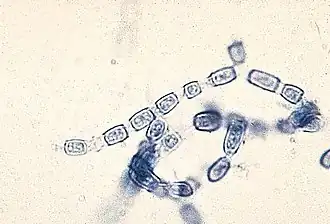

Arthroconidien von Coccidioides immitis | ||||||||||||

Coccidioides immitis ist ein pathogener Schlauchpilz und der Verursacher der Kokzidioidomykose. Der Pilz besitzt ein 29 Mb großes haploides Genom. Coccidioides immitis ist entfernt mit dem ebenfalls dimorphen Pathogen Histoplasma capsulatum verwandt. Zum Überleben in Säugetiergewebe besitzt er Proteasen und Keratinasen. Zudem produziert er Toxine. Tannasen zum Abbau von pflanzlichen Geweben kann C. immitis hingegen nicht mehr produzieren.[1] Bei Feuchtigkeit vermehrt sich der Pilz und bildet dabei eine enorme Menge Sporen. In der Trockenheit verbreiten sich die Sporen.[2]